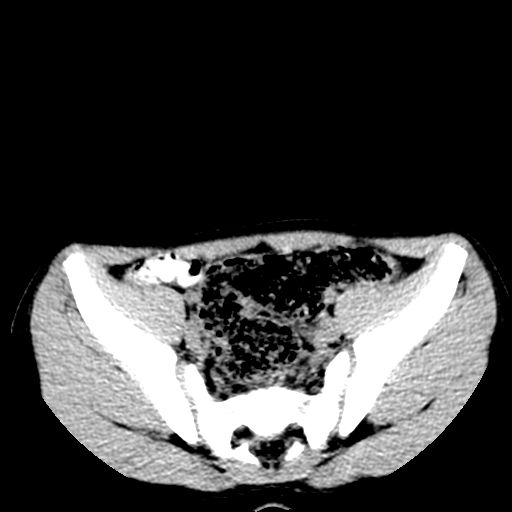

标题: PED3104:男,7岁,反复腹痛3年,再发2天。WBC:10.8X10 9/L,粪 [打印本页]

标题: PED3104:男,7岁,反复腹痛3年,再发2天。WBC:10.8X10 9/L,粪

右肺多发斑片状,点条状病灶,密度不均,边界较清晰,可见点状钙化。纵隔内见多发淋巴结钙化。应该考虑肺结核可能大。反复腹痛是否有腹腔结核或肠结核?

胸部明显是成年女性,定位象上双侧补过牙齿。轴位像上双侧乳腺退化。可以认定胸部与腹部不是一个人。

1)右肺继发性肺结核并右肺上叶节段性肺不张,支气管扩张。2)纵隔内多发淋巴结钙化。

腹部好象未见异常。

腹部ct平扫未见明确异常